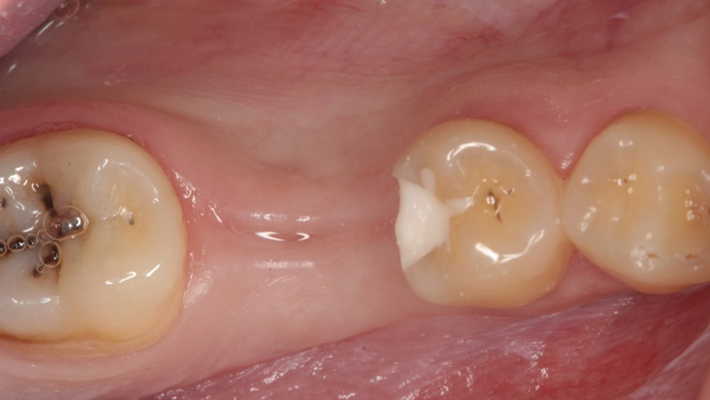

Clinical case: # 46 implant placement & GBR using i-Gen membrane for significant vertical resorption & mixed bone defect

- Courtesy of Dr. Iulian Filipov, Romania -

AnyRidge, mandibular posterior, i-Gen, resorption, bone defect, bone regeneration, space management, #46, GBR, Dr. Iulian Filipov

“AnyRidge KnifeThread achieves excellent stability in regenerated bone & even in only 3mm bone height!”